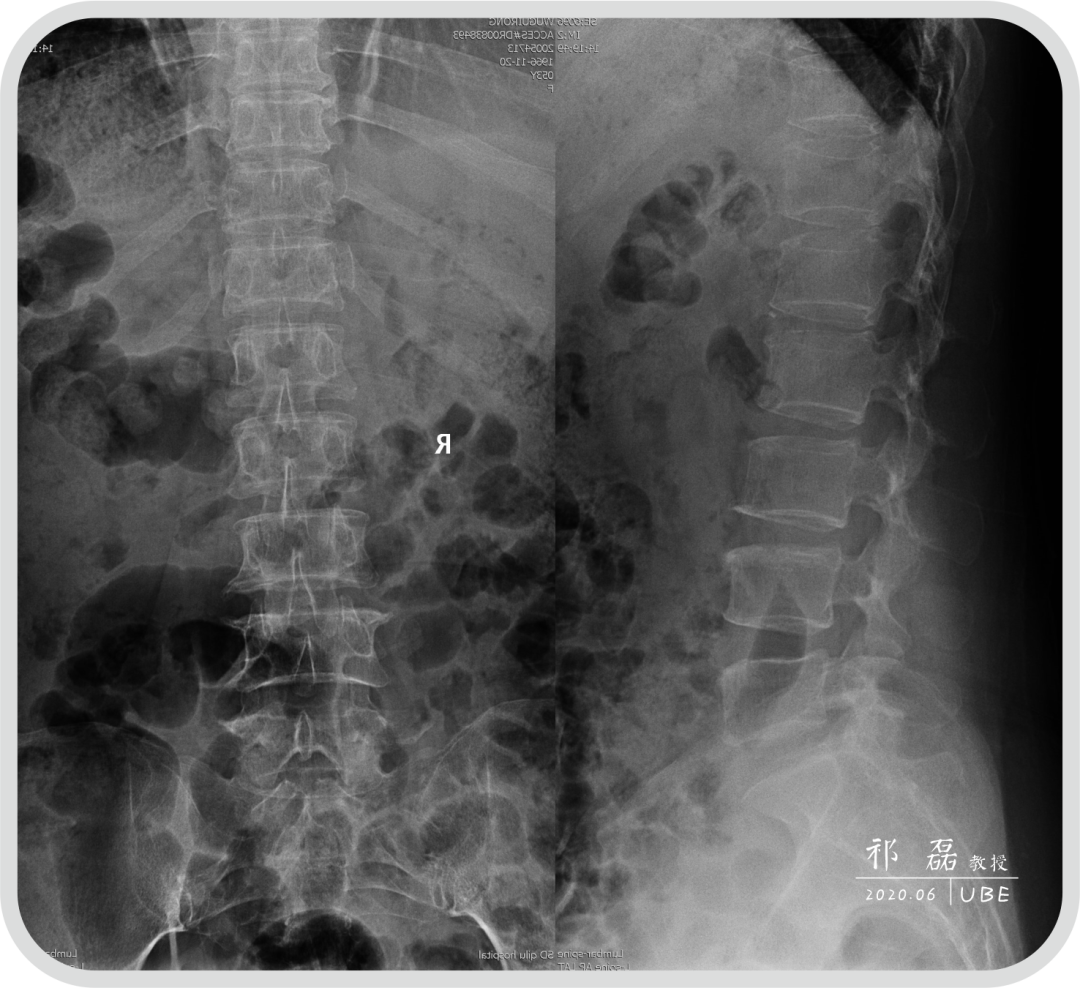

患者:吴某,女,53岁,腰痛及双下肢疼痛麻木5年余,加重1月余,间歇性跛行约200米。于近日入我院查体,下腰椎棘突及椎旁肌深压痛,双下肢感觉运动正常。双侧直腿抬高试验(-),双侧踝反射(-),入院诊断为:腰椎管狭窄症。

图2:腰椎CT